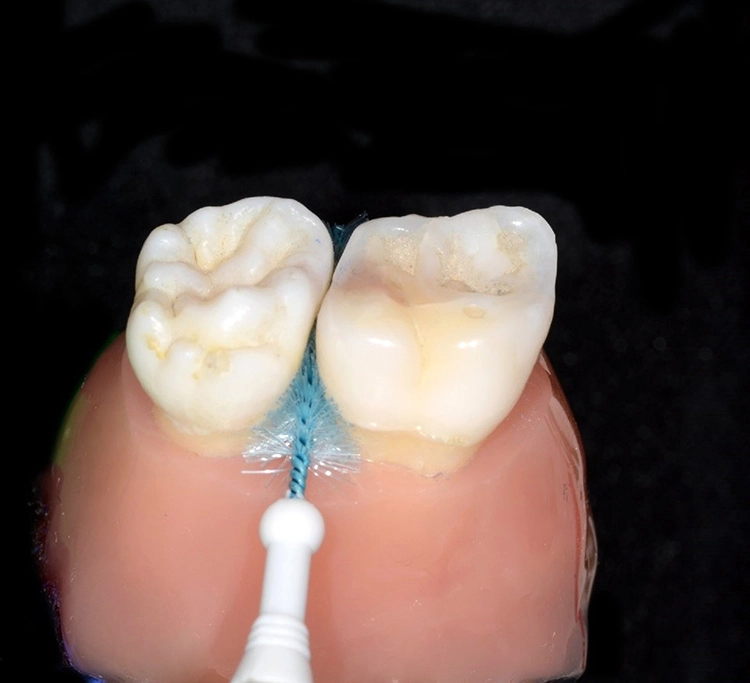

In der Praxis werden an Patienten zuweilen mit Messsonden diverse Größen ausprobiert, um eine entsprechende Empfehlung abzugeben [26]. Allerdings ist ihr Wert umstritten. Eine korrekt angepasste Interdentalraumbürste sollte den kompletten Interdentalraum reinigen und mit „mittlerem“ Druck ein- und auszuführen sein. Wenn sie zu dünn ist, hat sie eine zu geringe Reinigungswirkung; ist sie hingegen zu dick, besteht Traumatisierungsgefahr. Abbildung 2 zeigt die Einprobe und Auswahl am Beispiel des Interdentalraums 41/42.